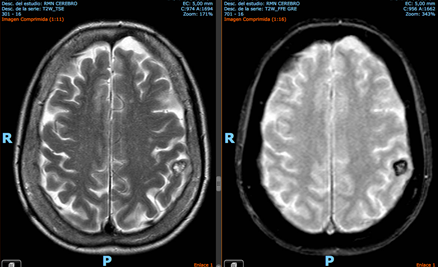

Ej. 1. Paciente con cavernoma incidental subinsular izquierdo en paciente joven que, en IRM de control, demostró crecimiento de la lesión y se decidió cirugía con buena evolución.

Ej. 2: Paciente de 70 años, antecedente de pérdida de memoria, con IRM con cavernoma incidental poscentral izquierdo. No se indicó tratamiento.